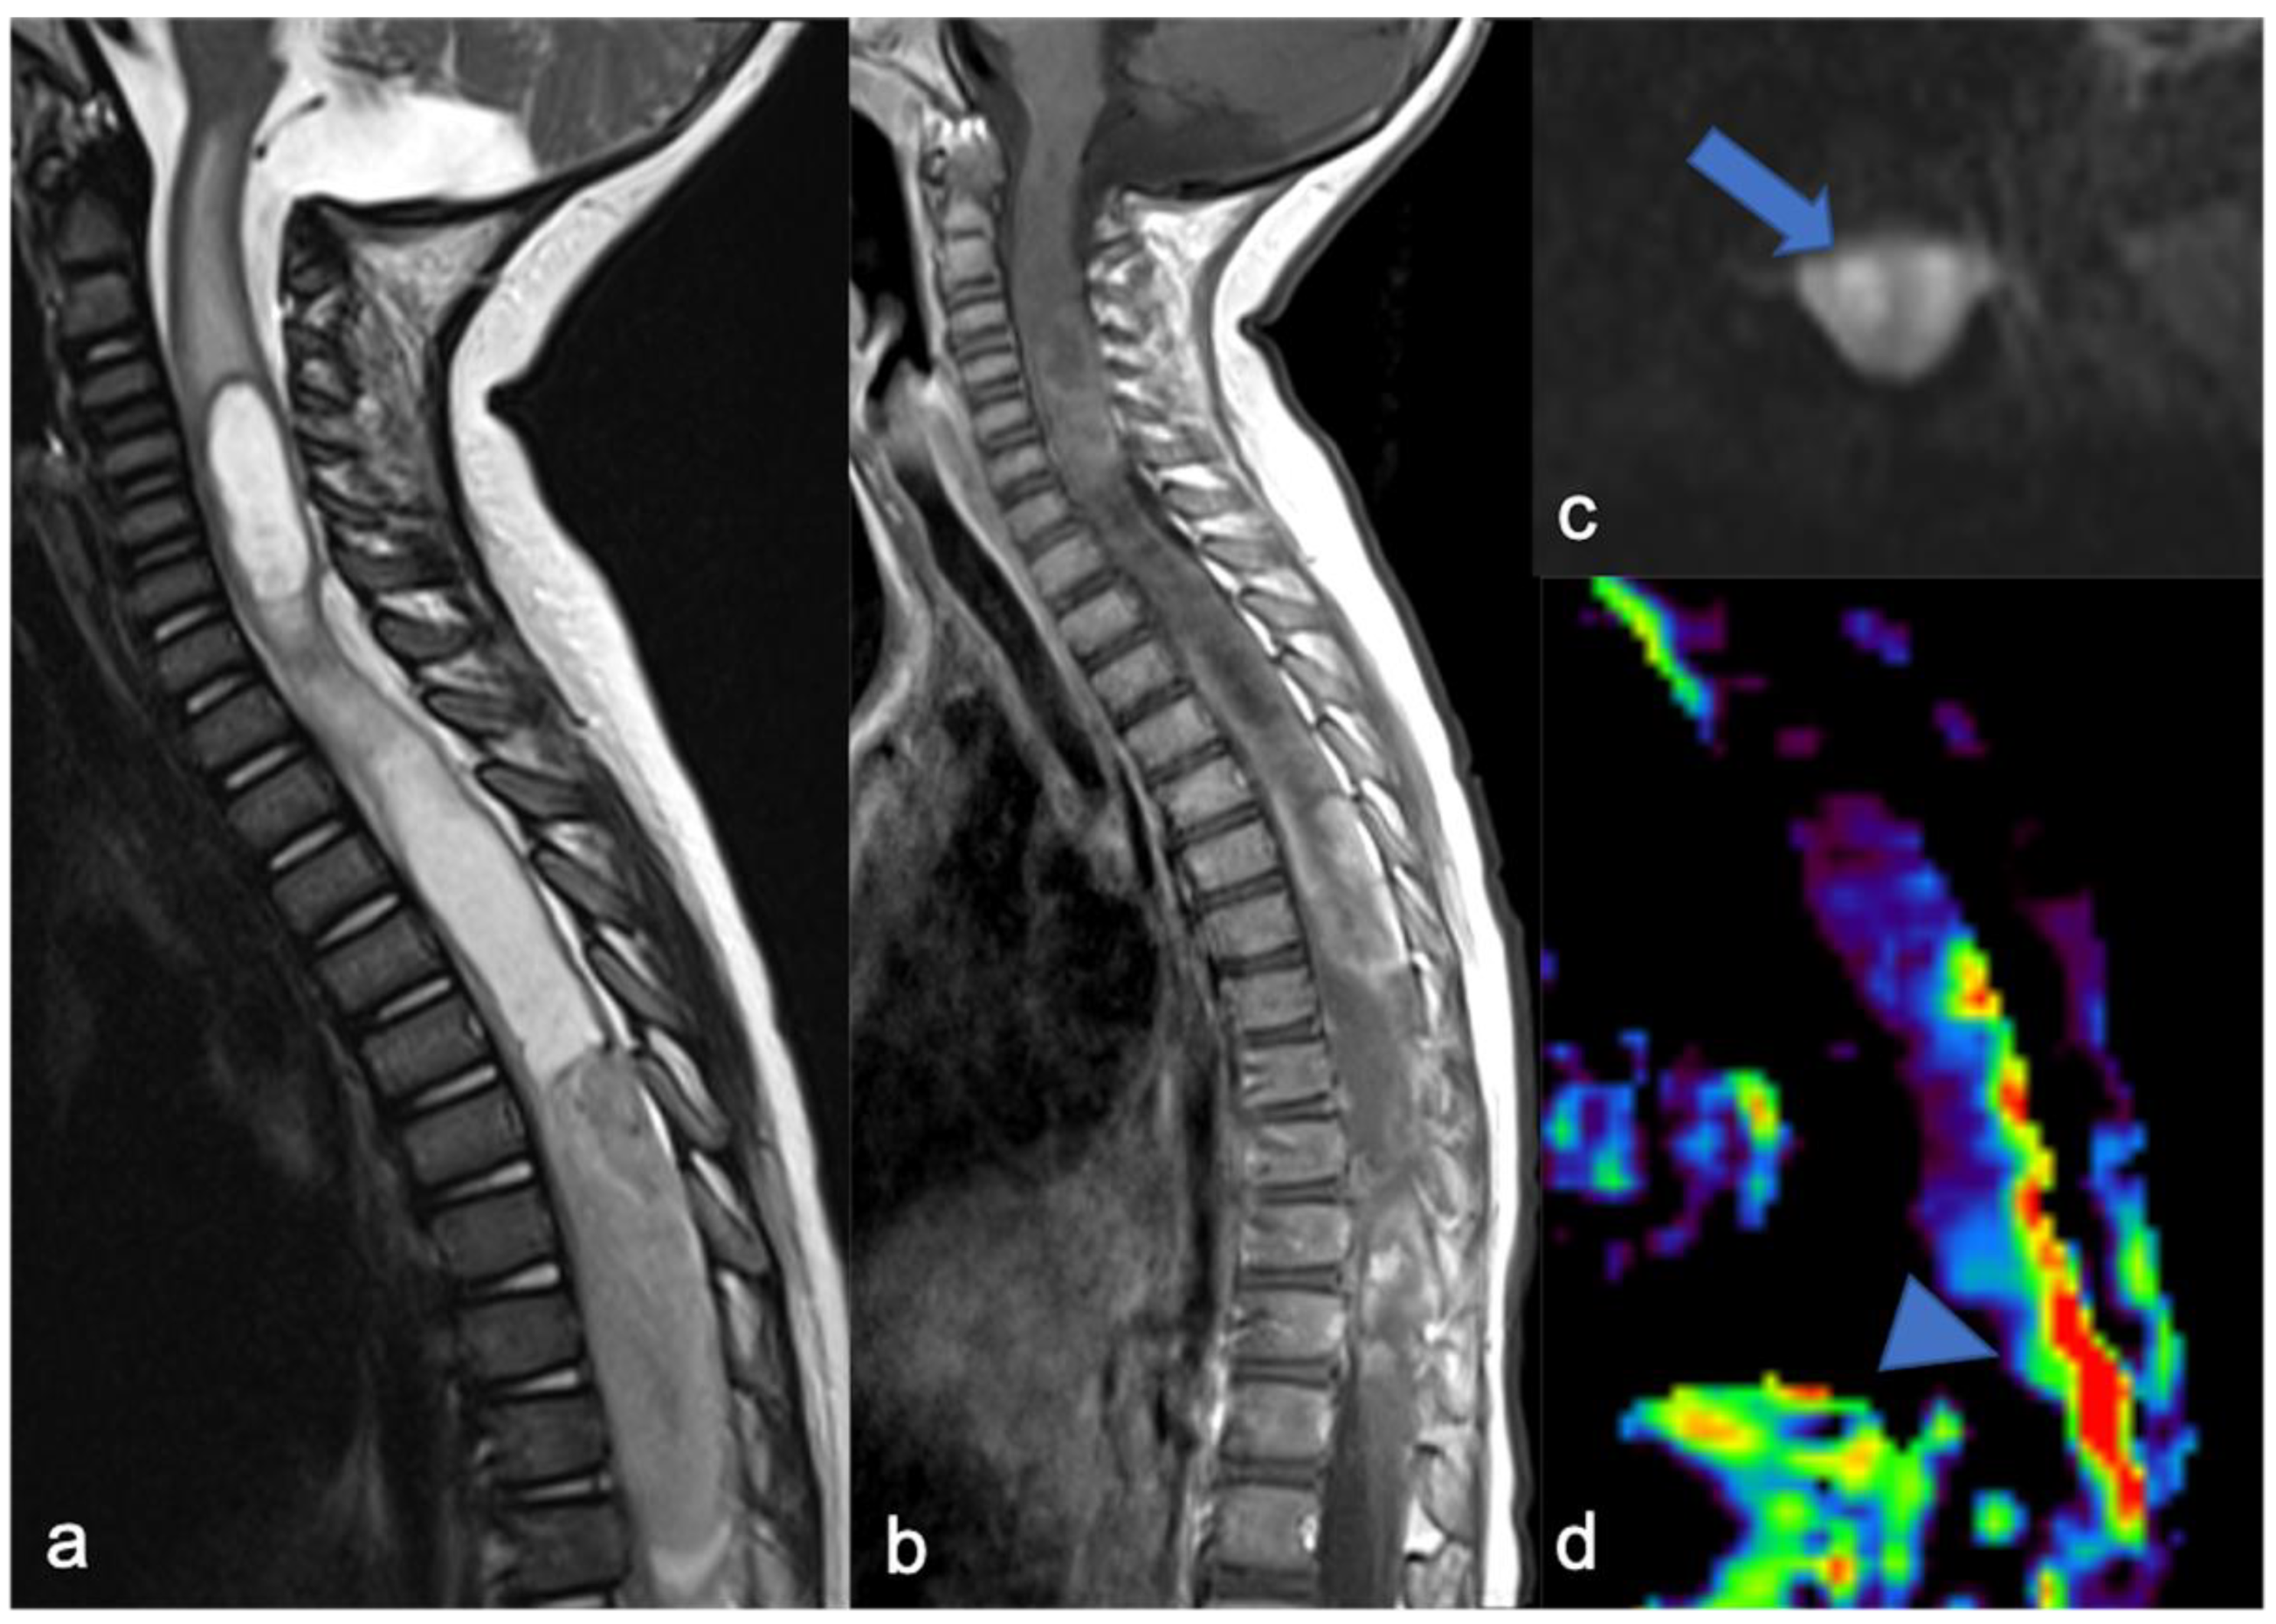

2.2. Diffuse Leptomeningeal Glioneuronal Tumor

- Gardiman, M.P.; Fassan, M.; Orvieto, E.; D’Avella, D.; Denaro, L.; Calderone, M.; Severino, M.; Scarsello, G.; Viscardi, E.; Perilongo, G. Diffuse Leptomeningeal glioneuronal tumors: A new entity? Brain Pathol. 2010, 20, 361–366. [Google Scholar] [CrossRef]

- Chiang, J.C.H.; Harreld, J.H.; Orr, B.A.; Sharma, S.; Ismail, A.; Segura, A.D.; Ellison, D.W. Low-Grade spinal glioneuronal tumors with BRAF Gene fusion and 1p deletion but without leptomeningeal dissemination. Acta Neuropathol. 2017, 134, 159–162. [Google Scholar] [CrossRef]

- Deng, M.Y.; Sill, M.; Chiang, J.; Schittenhelm, J.; Ebinger, M.; Schuhmann, M.U.; Monoranu, C.-M.; Milde, T.; Wittmann, A.; Hartmann, C.; et al. Molecularly defined diffuse leptomeningeal glioneuronal tumor (DLGNT) Comprises two subgroups with distinct clinical and genetic features. Acta Neuropathol. 2018, 136, 239–253. [Google Scholar] [CrossRef]

- Peer, S.; Murumkar, V.; Kulanthaivelu, K.; Prasad, C.; Rao, S.; Santosh, V. Diffuse Leptomeningeal glioneuronal tumor with high-grade features masquerading as tubercular meningitis—A case report. Egypt. J. Radiol. Nucl. Med. 2021, 52, 146. [Google Scholar] [CrossRef]